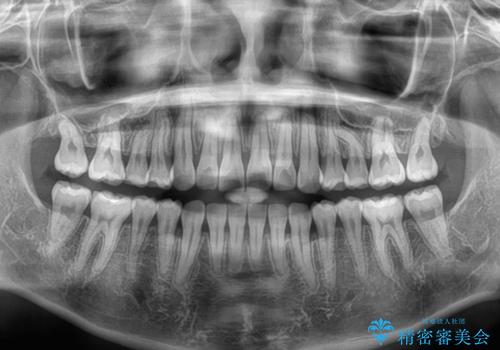

捻れて前に出ている前歯 ワイヤー装置での非抜歯矯正

- 捻れて前に出ている上顎前歯と全体的なデコボコを気にして来院された患者様です。

口元の突出感は強くなかったため非抜歯矯正での対応となりますが、捻転を改善する際に上顎前歯が前突する可能性があったため、上顎臼歯部にアンカースクリューを使用して、歯列が前方に転位しないようにすることとしました。

また舌のトレーニングを行うことで、上顎前歯の突出予防や上下前歯に隙間ができなくなるようにしました。

ワイヤー矯正でもインビザラインでも対応可能でしたが、上顎歯列が前方位であるときには、ワイヤー矯正の方がより良い仕上がりとなる可能性が高いため、ワイヤー矯正をおすすめいたしました。

舌の突出癖がなかなか改善されず、上下前歯が接触するようになるまでに長期間を要しました。